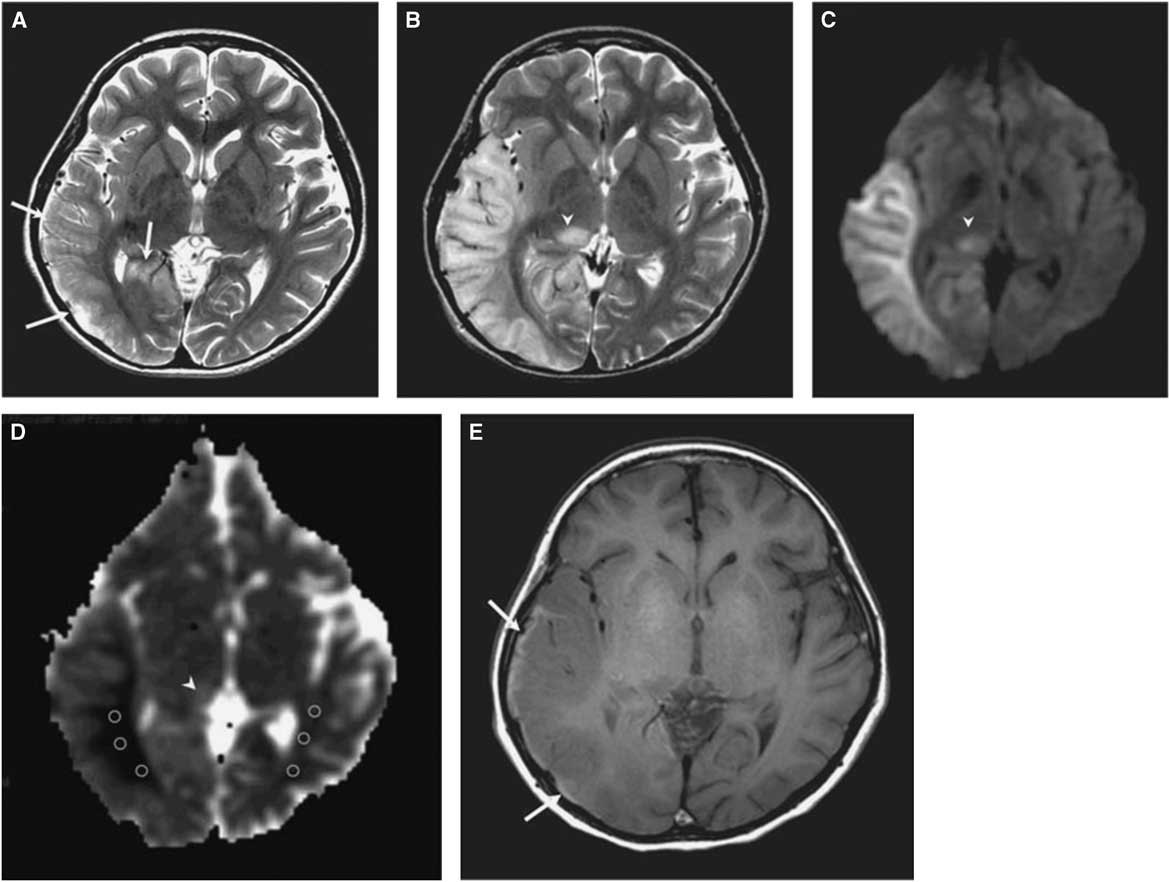

The morphological correlate of an SLE on cerebral imaging is the stroke-like lesion (SLL). Depending on the interval after onset, an acute or chronic stage of an SLL can be delineated. The acute stage of an SLL on magnetic resonance imaging (MRI) is characterized by hyperintensity on T2-w/fluid-attenuated inversion recovery images, hyperintensity on diffusion weighted imaging (DWIs), and hyperintensity on apparent diffusion coefficient (ADC) maps (Figure 1). Occasionally, areas with cytotoxic edema within the SLL may be found. Blood flow is increased on perfusion weighted imaging in the acute stage. Magnetic resonance spectroscopy may show a lactate peak and a reduced N-acetyl-aspartate/creatine ratio indicating neuronal death (Table 2).Reference Wang, Xiao, Xie, Zhao, Liu, Zhang, Yuan and Huang 19 , Reference Finsterer 20 A lactate peak is regarded as abnormal only if the N-acetyl-aspartate/choline ratio is normal. In a study of 13 patients with, altogether, 44 SLLs, DWI showed hyperintensity in 37 and isointensity in seven cases.Reference Kim, Lim and Jeon 21 On ADC, 16 were hyperintense, 16 hypointense, and 15 isointense.Reference Kim, Lim and Jeon 21 The chronic stage of SLLs is characterized by spreading and later regression of the lesion, hyperintensity, hypointensity, or isointensity on T2,Reference Kim, Lim and Jeon 21 hyperintensity, fainting or disappearance on DWI, hypointensity or isointensity on ADC, and hypoperfusion.Reference Wang, Xiao, Xie, Zhao, Liu, Zhang, Yuan and Huang 19 Outcomes from SLLs include complete recovery, focal atrophy, laminar cortical necrosis, or a WML.Reference Kim, Lim and Jeon 21 , Reference Renard and Taieb 22 Besides SLEs, patients with MIDs may experience ordinary ischemic strokes or transitory ischemic attacks secondary to cardiac involvement in the MID.Reference Mitani, Aida, Tomiyasu, Wada and Osaka 23 SLEs are frequently accessible to the nitric oxide precursors L-arginine (500 mg/kg/d), citrulline, or succinate. Supportive measures include a ketogenic dietReference Steriade, Andrade, Faghfoury, Tarnopolsky and Tai 24 and symptomatic treatment of the various clinical manifestations of an SLE.Reference Finsterer and Bindu 25

Figure 1 (A) T2-weighted image obtained at day 3 after onset of an SLE shows mild swelling (arrows) of right temporo-occipital lobe. (B) T2-weighted image obtained at day 11 after onset shows progression of edema in the right temporo-occipital lobe and newly appearing thalamic lesion (arrowhead). (C) Hyperintensity of affected areas (arrowhead) on DWI. (D) Hypointensity of the white matter and hyper-/isointensity of the cortex and thalamus on ADC (arrowhead). (E) T1-weighted image shows hyperintense rim (arrows) along cortex of swollen right temporo-occipital lobe, suggesting cortical laminar necrosis. (Reproduced from Kim et al. Korean J Radiol. 2011;12:15-24, with permission.)